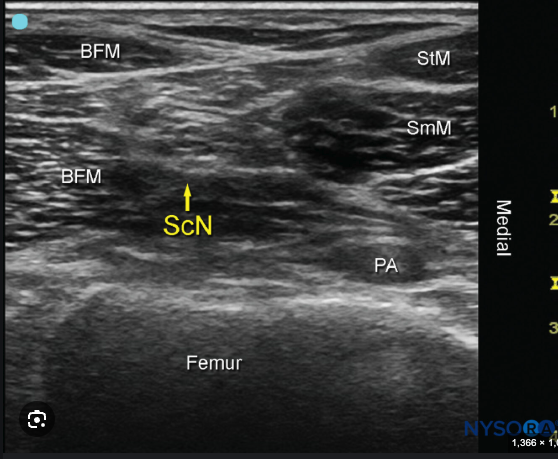

Q

Popliteal Sciatic nerve

A

20 mL

Save 5 -10 for saphenous